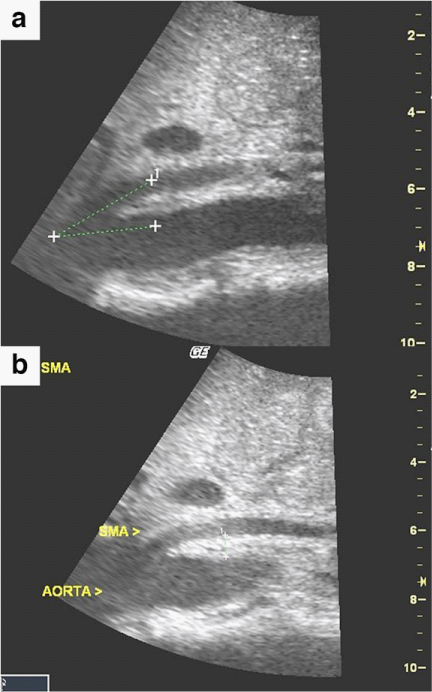

A 62 year-old African American man presented with periumbilical abdominal pain, nausea and bilious, non-bloody vomiting for two days. One month prior to presentation he was evaluated for a four-month history of watery, non-mucoid diarrhea with associated 15 lb unintentional weight loss. This workup included stool studies, colonoscopy, and CT of the abdomen, all of which were normal. His medical history was notable for uncontrolled diabetes mellitus type II, seizure disorder, and untreated hepatitis C. On examination he was a cachectic male with a calculated BMI of 14.8. He was hemodynamically stable and afebrile, with a diffusely tender abdomen and voluntary guarding. There were no stigmata of liver disease. Laboratory studies revealed a leukocytosis of 15.9; however an extensive infectious work-up including blood, urine and peritoneal cultures was negative. Liver function tests, amylase, lipase, and lactate levels were all normal. A CT of the abdomen revealed narrowing of the distance between the SMA and the aorta at the level of the 3rd portion of the duodenum (Figure 1a), with associated dilation of the stomach and proximal duodenum. These findings were consistent with SMA syndrome. Also seen were non-occlusive thrombi in the branches of the portal vein consistent with acute PVT (Figure 1b). Finally, mild compression of the distal superior mesenteric vein (SMV) was appreciated on CT. An abdominal ultrasound revealed a decreased SMA-aortic angle of 16-24 degrees (Figure 2a) and a distance between the two measuring 6mm (Figure 2b), thereby confirming the diagnosis of SMA syndrome.4 Esophagogastroduodenoscopy (EGD) was subsequently performed, revealing a dilated stomach with large amounts of gastric contents. A decompressive gastrostomy tube with a feeding jejunal extension was placed. The patient was managed medically with anticoagulation and empiric antibiotics and demonstrated clinical improvement. He was subsequently discharged to a nursing facility following a 2 week hospitalization; the gastrojejunostomy tube was kept in place on discharge. The patient returned to the hospital 2 months later with urosepsis further complicated by diabetic ketoacidosis and uncontrolled seizures. The patient ultimately expired from these comorbid illnesses before follow-up imaging could be obtained.

Figure 2(a) Sagittal ultrasound image of the abdomen demonstrates a decreased superior mesenteric artery-aortic angle of approximately 16-24 degrees.

(b) Sagittal Abdominal ultrasound image demonstrates a decreased distance between the aorta and the superior mesenteric artery of 6 mm.